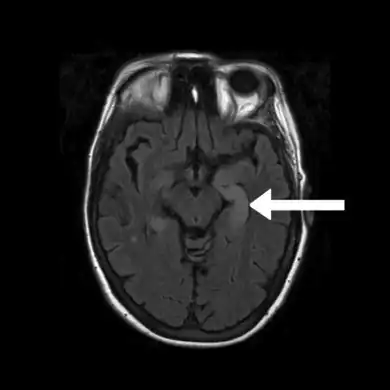

FLAIR MRI-Indicates bright signal from medial temporal lobe consistent with limbic encephalitis arrow

Brain MRI is the mainstay of initial investigation pointing to limbic lobe pathology revealing increased T2 signal involving one or both temporal lobes in most cases.[22][14]

Serial MRI in LE starts as an acute disease with uni- or bilateral swollen temporomesial structures that are hyperintense on fluid attenuation inversion recovery and T2-weighted sequences. Swelling and hyperintensity may persist over months to years, but in most cases progressive temporomesial atrophy develops.[23]